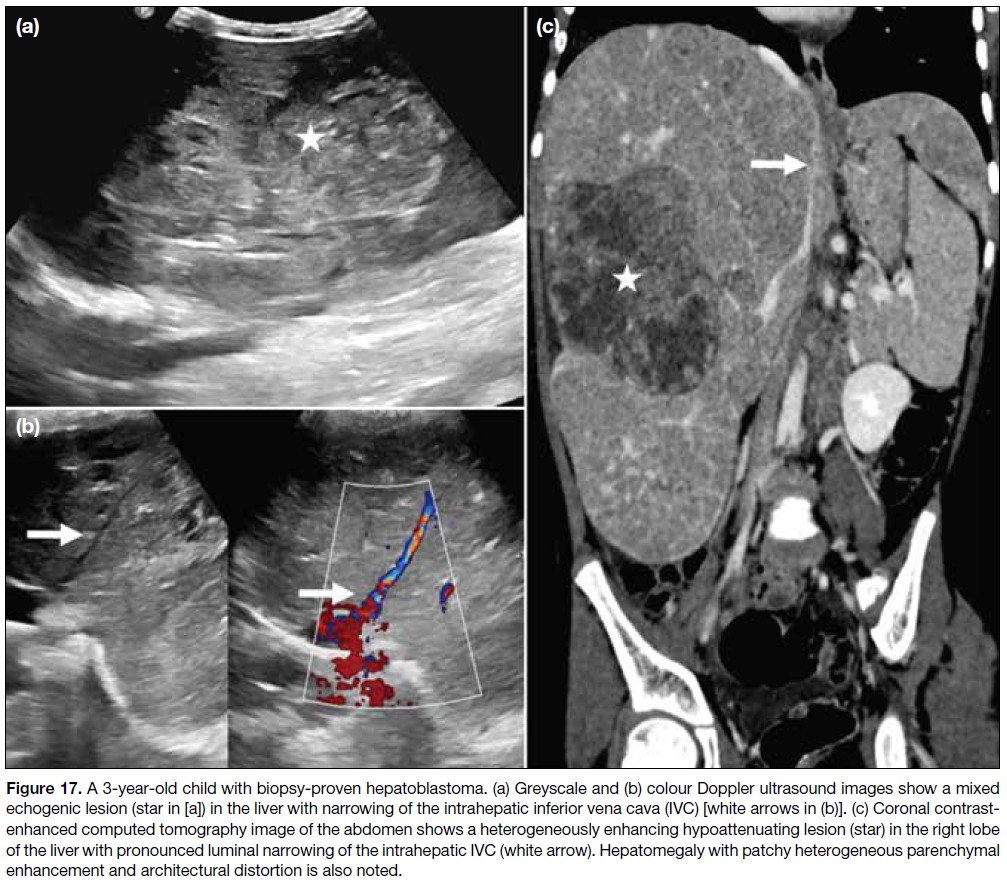

Anatomical variants in the hepatic vasculature and the

IVC should be identified before segmental resection

in hepatoblastoma (Figure 17). Retroperitoneal

malignancies in children may involve the abdominal

vasculature, including the IVC (Figure 18). Thrombosis

and vascular displacement are more common in Wilms

tumours than vessel encasement, whereas vascular

invasion occurs more frequently in neuroblastomas[4] (Figure 19).

Figure 17. A 3-year-old child with biopsy-proven hepatoblastoma. (a) Greyscale and (b) colour Doppler ultrasound images show a mixed

echogenic lesion (star in [a]) in the liver with narrowing of the intrahepatic inferior vena cava (IVC) [white arrows in (b)]. (c) Coronal contrast-enhanced

computed tomography image of the abdomen shows a heterogeneously enhancing hypoattenuating lesion (star) in the right lobe

of the liver with pronounced luminal narrowing of the intrahepatic IVC (white arrow). Hepatomegaly with patchy heterogeneous parenchymal

enhancement and architectural distortion is also noted.